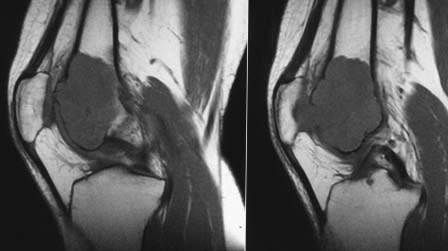

прилагаю МРТ и КТ. Образование накапливает радифармпрепарат :(

Снимки

Внешне похоже на ОБК. Другой вариант - аневризмальная киста, но вряд ли (на МРТ обычно видны множественные уровни жидкости).